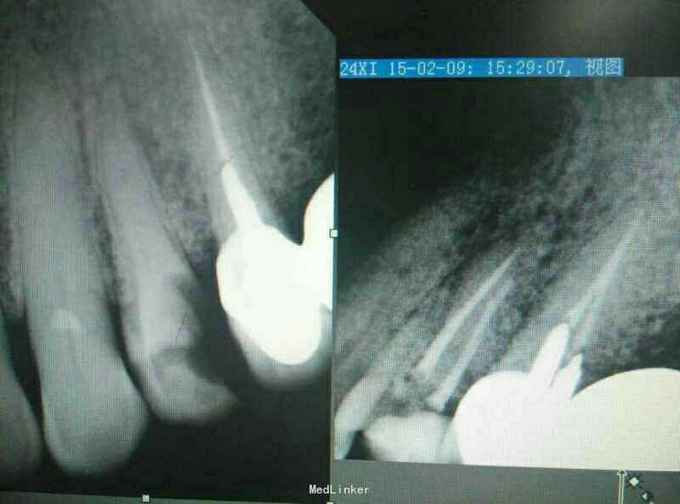

想兼职被要求发病例当代表作,手机里只有今年一月份随手拍下来的当月的几张病例X光片,发出来权当代表作,欢迎大家批评指正。主要是拔牙和根管治疗。

后牙根管再治疗